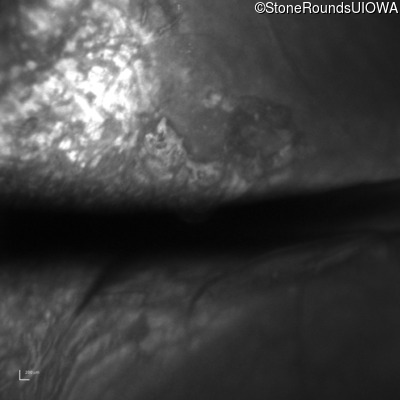

Optical Coherence Tomography - Right - 20/200 sc

Exemplar / OCT Stack